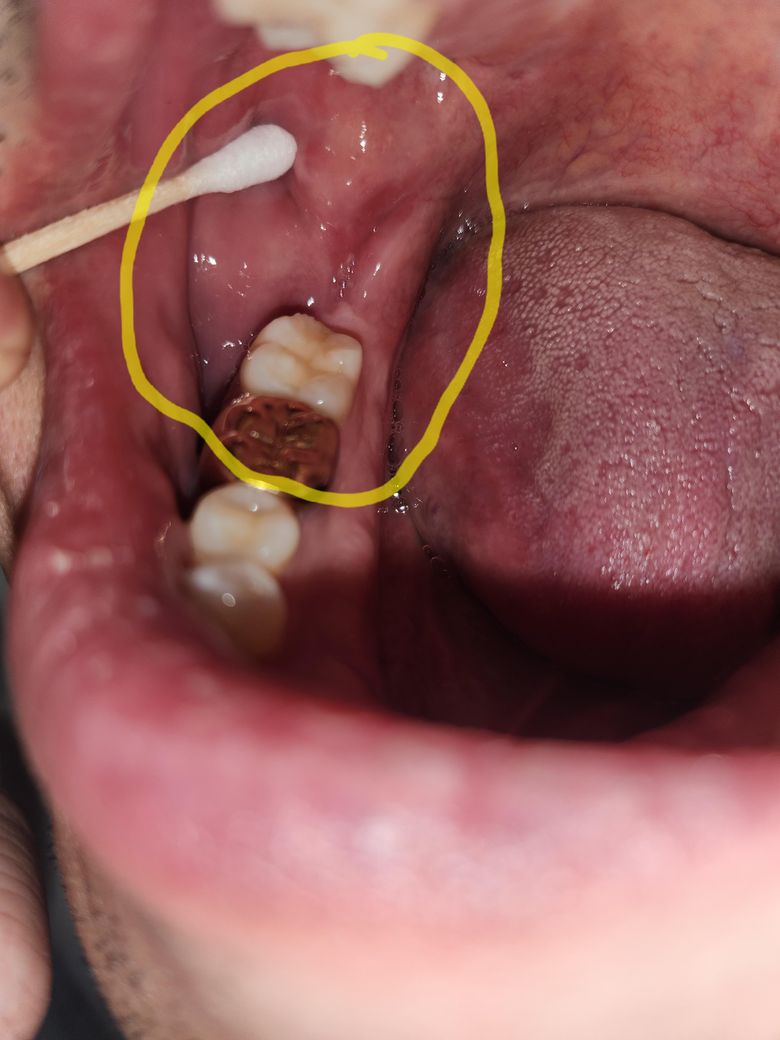

볼 안쪽 살 볼록해서 접힘 (기존 이갈이 협점막 백선 있음)

기존에 수면 이갈이가 심해서 협점막 백선 생김

수개월째 반복중,

연고 바르고 있고 스플린트도 사용중

이갈이랑 연관이 있을지 없을지 모르겠는데

양 볼 안쪽 살이 많이 볼록해서 접히는데

원래 이렇게까지는 아니었어요

(전반적으로 입안쪽 수개월 전부터 이상생김, 지속적)

1.접히는 부분 들춰보면 새빨간데 문제없나요?

2.볼 안쪽살이 볼록해서 접히는 이유가

이갈이에 의한 데미지, 붓기 인가요?

3.살찌면 뱃살나오듯이 단순 볼살 인가요?

4.대학병원 가게된다면 치과,구강내과,구강외과,

이비인후과 어디를 가면 적절한가요?

• 1번 째 사진

치아에 가해지는 힘이 너무강하다면 볼이 안쪽으로 밀리면서 백선이 생기거나 손상으로 인해서 혈종등이 생길수 있습니다 해당증상은 치아에 가해지는 힘을 줄어주면 줄어들수도 있습니다.

통증이 잇는게 아니라면 크게 걱정은 안하셔도 될것같습니다. 살이 접혀서 그럴수도 잇을것같습니다. 불편하시면 대학병원 구강내과를 가셔서 검진을 받아보시는게 좋을것같습니다.

아무래도 이갈이 기왕력이 있기 때문에 그 영향이 클 듯 한데 그 외에도 구강 내 바이러스나 세균 감염도 의심해볼 수 있습니다. 구강내과를 먼저 가보시는 것을 추천합니다.

볼살이 씹히면서 붓기가 생기고 계속 자극을 받는 것 같습니다. 구강내과로 가보시면 됩니다.

1.이정도는 문제되지 않습니다.

2.치아와 치아 사이에 볼살이 밀려 들어가 자국이 생긴 것입니다.

3.단순 볼살 맞습니다.

4.굳이 치과 안가도 됩니다. 만약 간다면 구강외과 추천합니다.